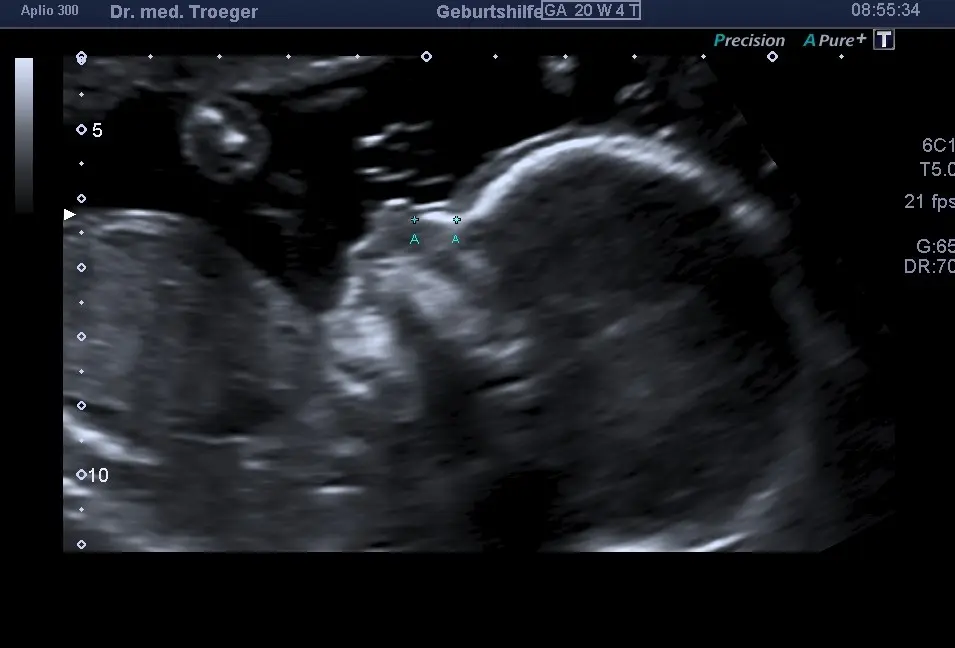

Gibt es eine Möglichkeit, das GA meines Kindes zu überprüfen?

Es gibt verschiedene Methoden, um das GA Ihres Kindes zu überprüfen. Ihr Arzt kann eine Ultraschalluntersuchung durchführen, um das GA Ihres Kindes zu bestimmen.